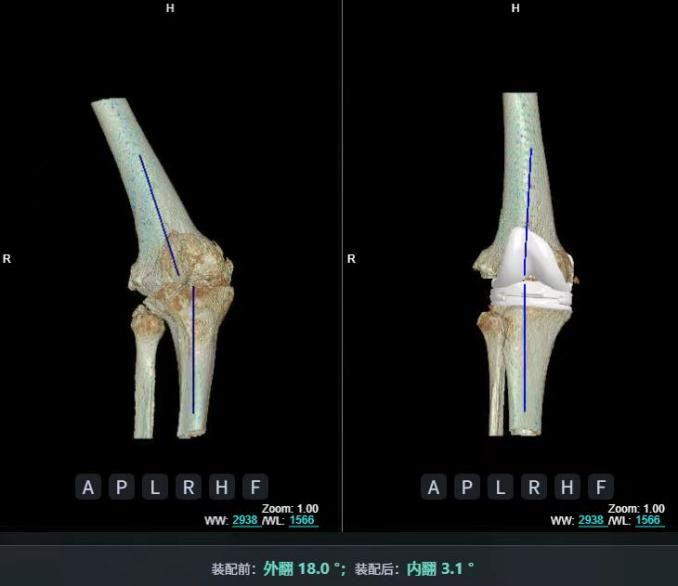

4.2 APTT-HTO脛骨高位截骨術(shù)

2025年7月,貴州醫(yī)科大學(xué)附屬醫(yī)院骨科團(tuán)隊(duì)原創(chuàng)研發(fā)的腘肌前結(jié)節(jié)中脛骨高位截骨保膝術(shù)(Anterior Popliteus Transtibial Tuberosity-High Tibial Osteotomy, APTT-HTO)及其提出的脛骨結(jié)節(jié)分區(qū)與腘肌保護(hù)理論,登上了國(guó)際頂尖學(xué)術(shù)舞臺(tái)。該成果在全球最具影響力的專業(yè)會(huì)議之一——日本骨科協(xié)會(huì)第98屆年會(huì)上進(jìn)行了兩次學(xué)術(shù)發(fā)言。[8]

該手術(shù)具有經(jīng)皮微創(chuàng)、保留原生膝關(guān)節(jié)結(jié)構(gòu)、符合階梯治療原則等優(yōu)勢(shì),通過調(diào)整下肢力線可促進(jìn)部分軟骨再生,術(shù)后關(guān)節(jié)功能接近正常(如下蹲、爬山),患者還能從事中重體力勞動(dòng)。相比其他術(shù)式,其有效規(guī)避了髕骨低位、血管損傷、合頁(yè)骨折等潛在并發(fā)癥。

目前,APTT-HTO技術(shù)已成功應(yīng)用于千余名患者,幫助保留自身膝關(guān)節(jié)。此類保膝手術(shù)適用于單間室膝關(guān)節(jié)炎患者(如 “羅圈腿”),核心是通過調(diào)整力線糾正畸形,減輕磨損間室壓力、發(fā)揮健康間室作用,延長(zhǎng)膝關(guān)節(jié)壽命。若出現(xiàn)膝關(guān)節(jié)疼痛、保守治療無(wú)效且X線顯示關(guān)節(jié)間隙部分狹窄,建議及時(shí)就醫(yī)評(píng)估是否適合手術(shù)。